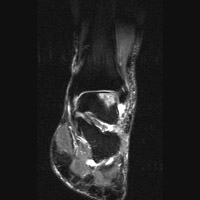

D | Sagittal MRI. This T1-weighted image shows a region of low signal intensity representing the site of osteochondritis dissecans and edema. |